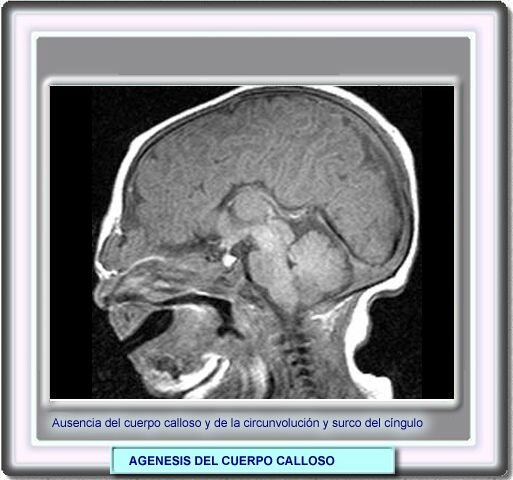

• Problema en el desarrollo: Agenesia cuerpo calloso

Problema en el desarrollo: Agenesia cuerpo calloso

Ausencia total o parcial del cuerpo calloso, asociado con convulsiones y deficiencia mental.